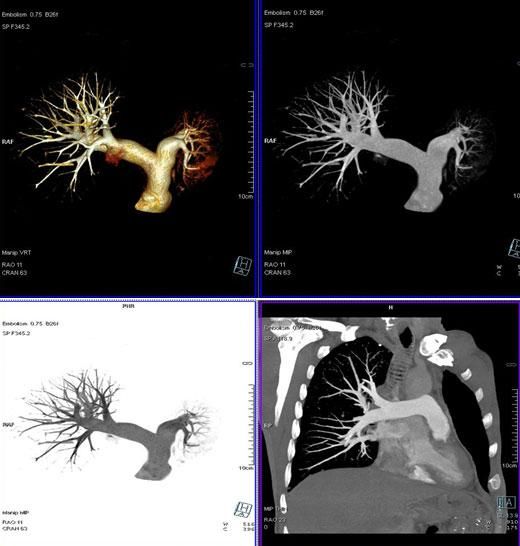

二、多層螺旋CT頭頸部及體部血管成像技術:

該機掃描覆蓋範圍廣、時間短,多種後處理分析軟件能顯示各血管細小分支,可以清晰顯示動脈瘤、動脈夾層、血管畸形、血管狹窄及動脈粥樣硬化斑塊等,适用于頭頸部血管成像、肺動脈成像、胸腹部血管成像及四肢血管成像。

3、肺動脈血管成像: